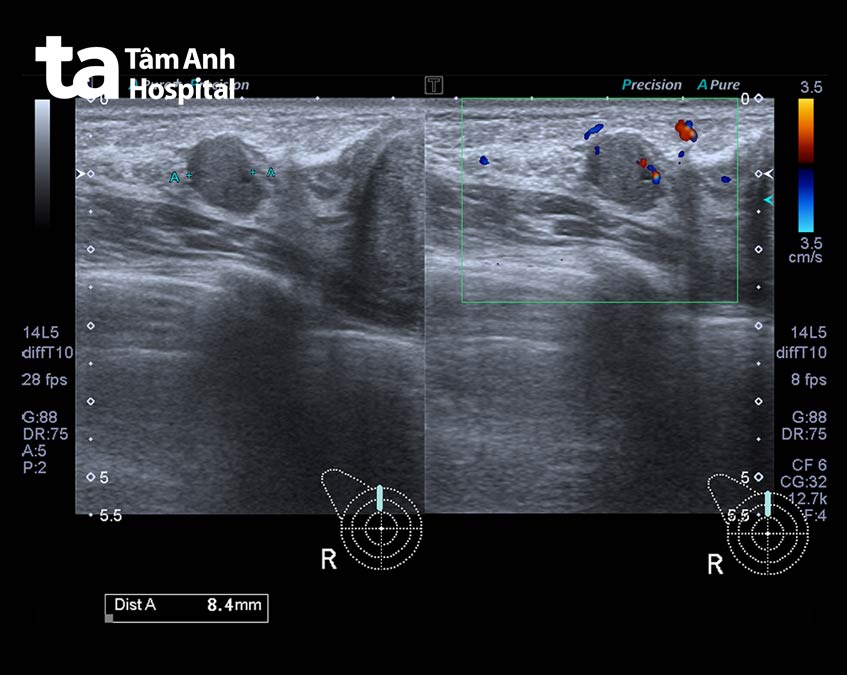

Nếu có bất kỳ dấu hiệu hoặc triệu chứng đáng ngờ, bác sĩ sẽ chỉ định siêu âm. Phương pháp chẩn đoán hình ảnh này sử dụng sóng âm để quan sát bên trong ngực, xác định xem khối u có rắn không. Đây là dấu hiệu của khối u ác tính.

Nếu khối u chứa đầy dịch, nhiều khả năng đây là u nang. Bác sĩ có thể sinh thiết (đưa 1 cây kim nhỏ vào khối u để lấy mô) và gửi mẫu mô đến chuyên gia giải phẫu bệnh để xác định u lành tính hay u ác tính.